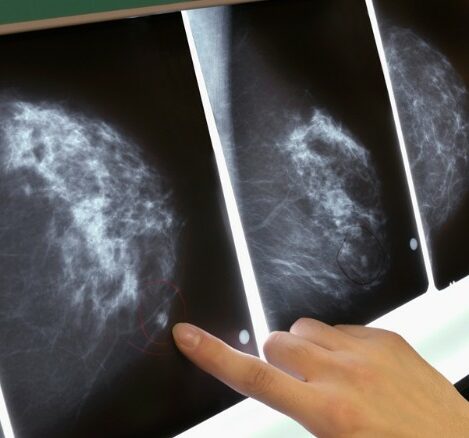

136 ndërhyrje për rindërtimin e gjirit u kryen në QKUK gjatë tri viteve të fundit